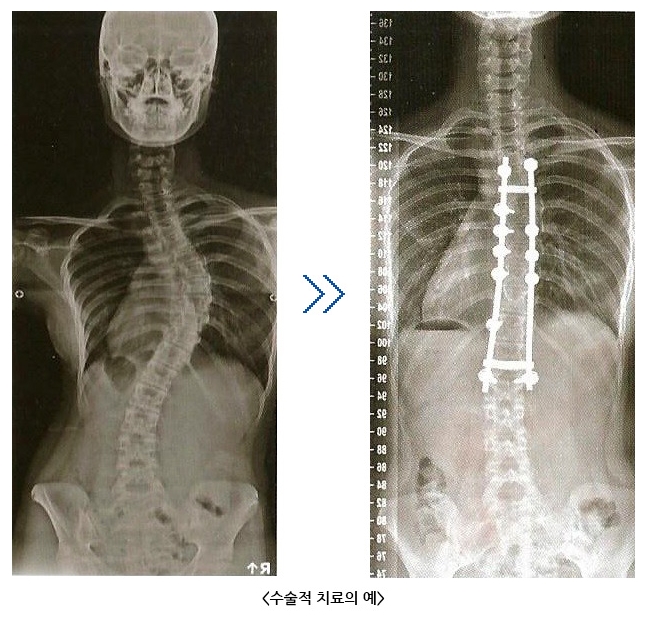

일반적으로 40~50도 이상의 만곡이 있는 경우는 적극적인 수술적 치료의 대상이 됩니다.

수술적 치료는 만곡의 진행을 막을 뿐만 아니라 상당한 정도의 변형을 직접 교정 할 수도 있습니다.